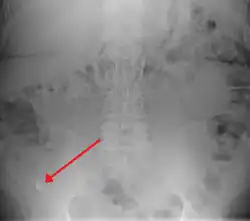

A fecalith marked by the arrow that has resulted in acute appendicitis.

Appendicolith as seen on plain X-ray.

In general, plain abdominal radiography (PAR) is not useful in making the diagnosis of appendicitis and should not be routinely obtained from a person being evaluated for appendicitis.[70][71] Plain abdominal films may be useful for the detection of ureteral calculi, small bowel obstruction, or perforated ulcer, but these conditions are rarely confused with appendicitis.[72] An opaque fecalith can be identified in the right lower quadrant in fewer than 5% of people being evaluated for appendicitis.[48] A barium enema has proven to be a poor diagnostic tool for appendicitis. While failure of the appendix to fill during a barium enema has been associated with appendicitis, up to 20% of normal appendices do not fill.[72]